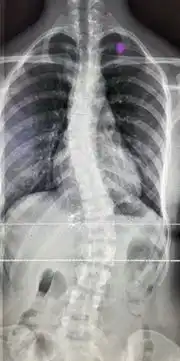

12岁男孩治疗2个月后,脊柱侧弯度数从30减至10

仅仅2个月,12岁男孩脊柱侧弯度数从30减至10